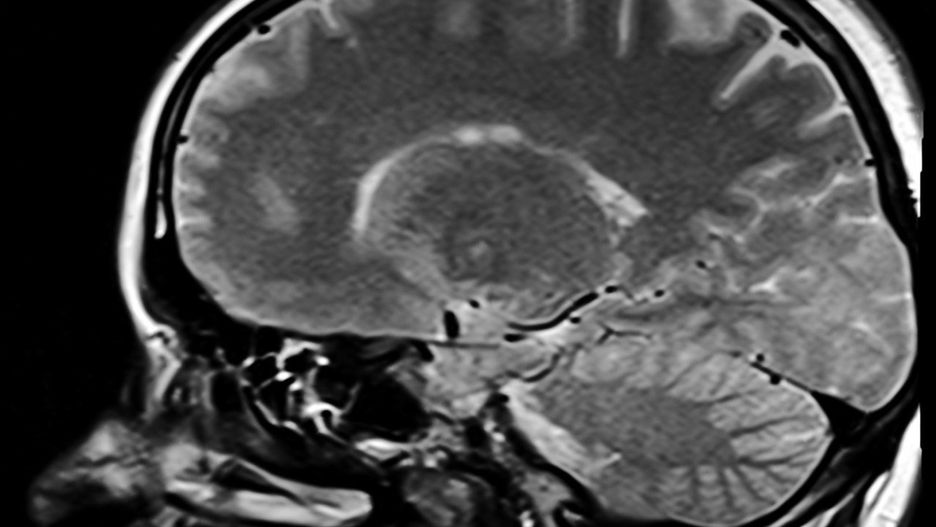

Utrata węchu lub smaku, bóle głowy, zmęczenie, zawroty głowy i nudności to częste objawy Covid-19. Jak udowadniają naukowcy z Berlina, są efektem przedostania się koronawirusa do mózgu.

Koronawirus powoduje poważne problemy neurologiczne. Naukowcy z Niemiec przeprowadzili sekcje zwłok 33 pacjentów zmarłych na Covid-19, aby móc dokładnie zbadać, jak oddziałuje na poszczególne organy wewnętrzne. Wyniki badań opublikowano 30 listopada w Nature Neuroscience.

Zbadano śluz z nosa, a także próbki tkanki mózgowej. Największe ilości koronawirusa były obecne w śluzie jamy nosowej, ale znaleziono je również w mózgu. Dr Frank Heppner, współautor badania stwierdził, że jest to wysoce prawdopodobnie, że to właśnie przez nos wirus dostaje się do mózgu.

Nasze dane sugerują, że wirus przemieszcza się z komórki nerwowej do komórki nerwowej, aby dotrzeć do mózgu. Jest jednak prawdopodobne, że wirus jest również przenoszony przez naczynia krwionośne, ponieważ dowody na obecność wirusa znaleziono również w ścianach naczyń krwionośnych –wyjaśnia dr Helena Radbruch pracująca nad tymi badaniami.

Obecność koronawirusa w mózgu nie jest niczym wyjątkowym. Inne wirusy także mogą się tam dostać m.in. wirus opryszczki, grypy i wścieklizny. Według naukowców może to tłumaczyć określone objawy Covid-19 takie jak utarta węchu, zawroty głowy czy też brak koncentracji.

Obecność wirusa w komórkach nerwowych błony śluzowej nosa stanowi dobre wyjaśnienie objawów neurologicznych występujących u pacjentów - takich jak utrata węchu czy smaku. Znaleźliśmy go również w obszarach mózgu, które kontrolują funkcje życiowe - takie jak oddychanie - wyjaśnia ekspert Profesor Heppner

Nie można zatem wykluczyć, że zaostrzone objawy również są zasługą przedostania się wirusa do mózgu. Mowa tu głównie o dusznościach i problemach z układem oddechowym.